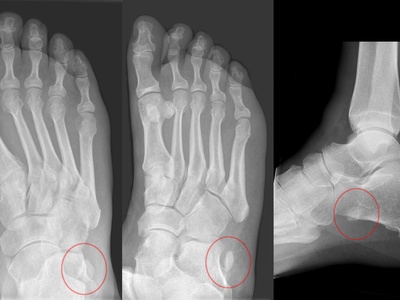

Medial sesamoid (hallux)

One of the two sesamoids beneath the big toe’s MTP joint, the medial sesamoid lies under the first metatarsal head in the flexor hallucis brevis tendon. It bears weight, aids push-off, and commonly causes pain when inflamed or fractured.

Lateral sesamoid (hallux)

The lateral sesamoid sits alongside the medial sesamoid beneath the first metatarsal head inside the lateral flexor hallucis brevis tendon. Together they act as pulleys during gait. They can fracture, become inflamed, or develop painful bipartite configurations.

Os peroneum

The os peroneum is a sesamoid inside the peroneus longus tendon near the cuboid bone. It helps tendon leverage and smooths tendon passage under the foot. It can fracture or cause lateral foot pain and is associated with peroneus longus tendinopathy.